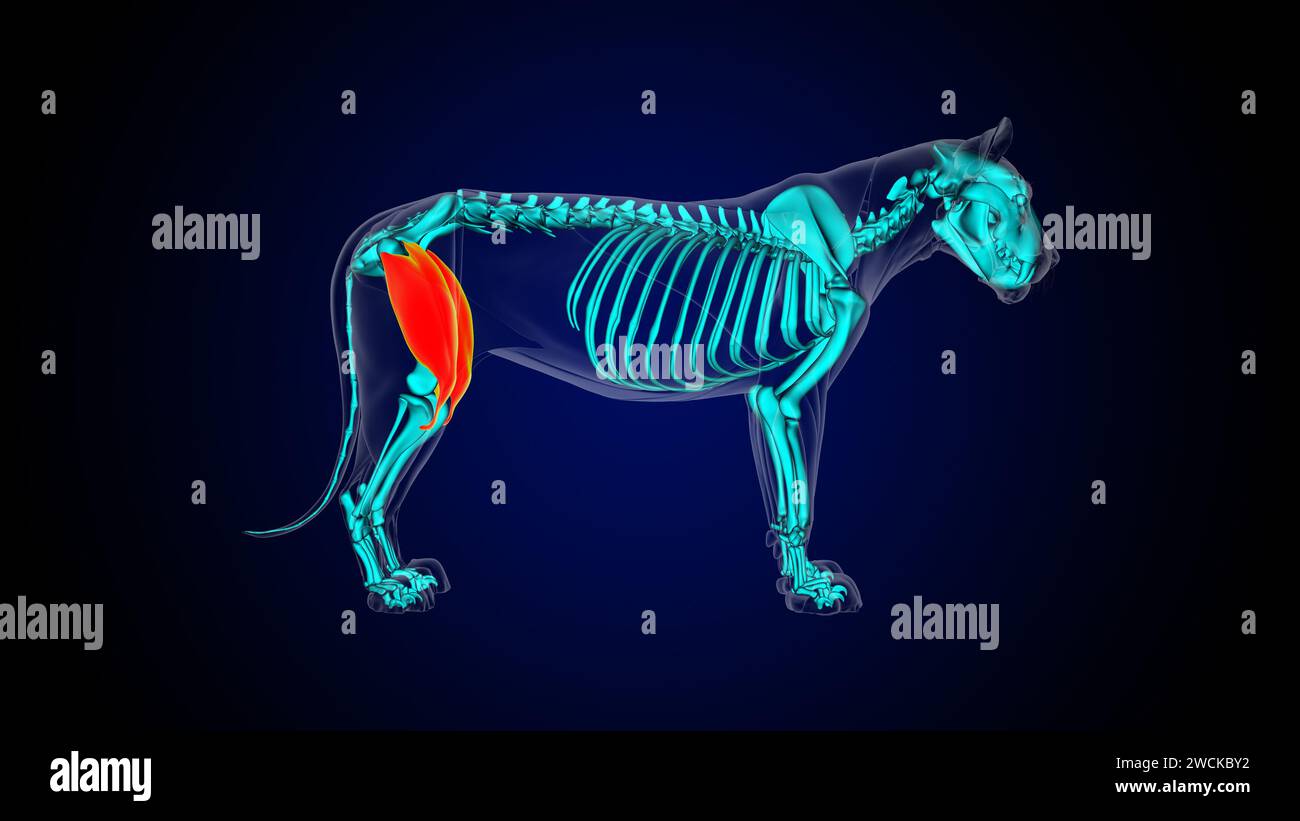

Muscle quadriceps anatomie musculaire du lion pour l'illustration 3D du concept médical Banque D'Imageshttps://www.alamyimages.fr/image-license-details/?v=1https://www.alamyimages.fr/muscle-quadriceps-anatomie-musculaire-du-lion-pour-l-illustration-3d-du-concept-medical-image592954838.html

Muscle quadriceps anatomie musculaire du lion pour l'illustration 3D du concept médical Banque D'Imageshttps://www.alamyimages.fr/image-license-details/?v=1https://www.alamyimages.fr/muscle-quadriceps-anatomie-musculaire-du-lion-pour-l-illustration-3d-du-concept-medical-image592954838.htmlRF2WCKBXE–Muscle quadriceps anatomie musculaire du lion pour l'illustration 3D du concept médical

Muscle quadriceps anatomie musculaire du lion pour l'illustration 3D du concept médical Banque D'Imageshttps://www.alamyimages.fr/image-license-details/?v=1https://www.alamyimages.fr/muscle-quadriceps-anatomie-musculaire-du-lion-pour-l-illustration-3d-du-concept-medical-image592954854.html

Muscle quadriceps anatomie musculaire du lion pour l'illustration 3D du concept médical Banque D'Imageshttps://www.alamyimages.fr/image-license-details/?v=1https://www.alamyimages.fr/muscle-quadriceps-anatomie-musculaire-du-lion-pour-l-illustration-3d-du-concept-medical-image592954854.htmlRF2WCKBY2–Muscle quadriceps anatomie musculaire du lion pour l'illustration 3D du concept médical